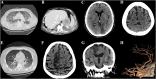

Background: Italy is one of the most affected countries by the coronavirus disease 2019 (COVID-19). The responsible pathogen is named severe acute respiratory syndrome coronavirus (SARS-CoV-2). The clinical spectrum ranges from asymptomatic infection to severe pneumonia, leading to intensive care unit admission. Evidence of cerebrovascular complications associated with SARS-CoV-2 is limited. We herein report six patients who developed acute stroke during COVID-19 infection.

Methods: A retrospective case series of patients diagnosed with COVID-19 using reverse-transcriptase polymerase chain reaction (RT-PCR) on nasopharyngeal swabs, who developed clinical and neuroimaging evidence of acute stroke during SARS-CoV-2 infection.

Results: Six patients were identified (5 men); median age was 69 years (range 57-82). Stroke subtypes were ischemic (4, 67%) and hemorrhagic (2, 33%). All patients but one had pre-existing vascular risk factors. One patient developed encephalopathy prior to stroke, characterized by focal seizures and behavioral abnormalities. COVID-19-related pneumonia was severe (i.e., requiring critical care support) in 5/6 cases (83%). Liver enzyme alteration and lactate dehydrogenase (LDH) elevation were registered in all cases. Four patients (67%) manifested acute kidney failure prior to stroke. Four patients (67%) had abnormal coagulation tests. The outcome was poor in the majority of the patients: five died (83%) and the remaining one (17%) remained severely neurologically affected (mRS: 4).

Conclusions: Both ischemic and hemorrhagic stroke can complicate the course of COVI-19 infection. In our series, stroke developed mostly in patients with severe pneumonia and multiorgan failure, liver enzymes and LDH were markedly increased in all cases, and the outcome was poor.